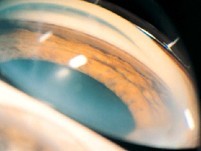

(如图)一位25岁男性,双眼没有疼痛,角膜边缘变薄,上皮仍完整,变薄区有黄色的脂质沉着物,下列说法正确的是()

-